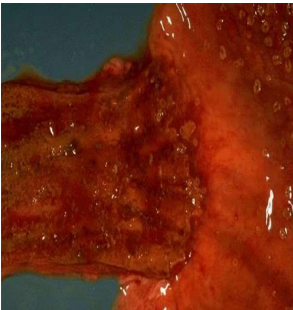

Here is another varix near the gastroesophageal junction that is dark red black because it has been

bleeding. (The esophagus has been turned inside out.)